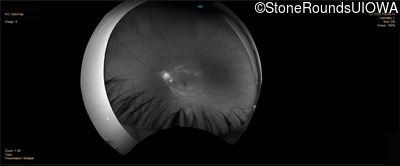

Infrared Fundus Photograph - Right - 20/20 -1 sc

Exemplar

Infrared Fundus Photograph - Left - 20/20 -1 sc